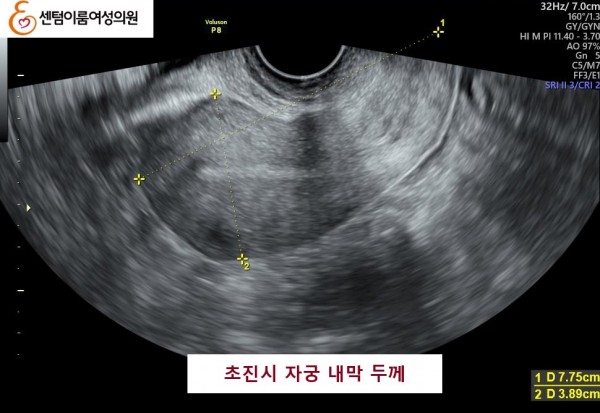

42세, 조 O O님 고령 연령에서 임신된 사례

2023.12월 본원 내원 전 타병원에서 시술 받으신 이력이 있으셨습니다.

40세 이상 고령 연령은 염색체 비정상 난자 비율이 높아 고난도 난임의 대표적인 사례입니다.

꾸준한 식생활 개선과 약물 치료후 임신에 성공 하셨습니다.